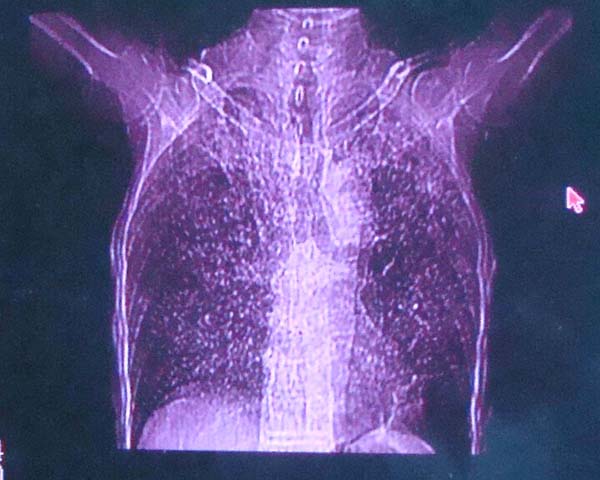

以下是引用zhangzhongshou在2008-2-15 22:25:00的发言:[br]片子照得不清,基本考虑1、细支气管肺泡癌2、亚急性血行播散型肺结核。请结合临床。片子细节显示不清,无法提供进一步意见。

以下是引用杀毒软件在2008-2-15 22:34:00的发言:[br]小叶中心性肺气肿。两肺弥漫性病变,肺泡微石病,过敏性肺炎,尘肺2期,特发性肺纤维化都有可能。[br]不象肺泡癌。